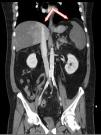

A 52-year-old patient with a history of ulcerative colitis consulted due to abdominal pain and rectal bleeding. The laboratory tests revealed liver cell necrosis and coagulation alterations, with acute phase reactant elevation and metabolic acidosis (lactate 10mmol/l). The abdominal CAT scan revealed massive arterial and venous thromboses (Fig. 1). Celiac trunk thrombosis was observed at the trifurcation, together with thrombosis affecting the splanchnic, left gastric and common hepatic arteries and respective branches, accompanied by extensive portal, superior mesenteric and splanchnic venous thrombosis, with massive infarction in the liver and spleen (Fig. 2). The clinical course proved negative and the patient died three days after admission. The cause of the arterial and venous thromboses could not be established.